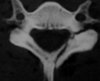

Fieldig Classification of AARD

Type I:

Unilateral facet subluxation with intact transverse ligament

Type II:

Unilateral facet subluxation with 3-5mm of anterior displacement (injured TL)

Type III:

Bilateral anterior facet displacement of >5mm

High risk of neuro compromise

Type IV:

Posterior displacement of Atlas (C1)